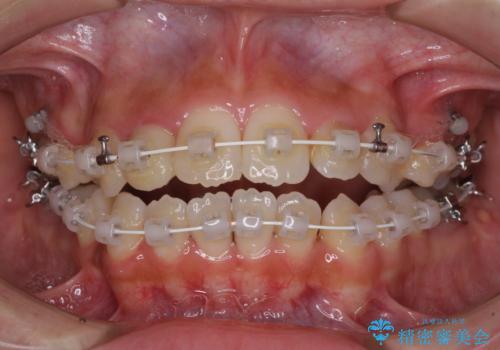

開咬と前突を改善 ワイヤー装置での抜歯矯正

- 矯正装置

- 審美装置

- 口元の突出感と開咬を気にして来院された患者様です。

口元の突出感を改善するため、第一小臼歯を抜歯して口元を引っ込めることとしました。

一般的には上下左右の第一小臼歯4本を抜歯しますが、下顎に対して上顎が前方に位置しているため、まずは上顎小臼歯2本を抜歯し、治療経過を見て下顎小臼歯を抜歯するかどうかを決めていくこととしました。